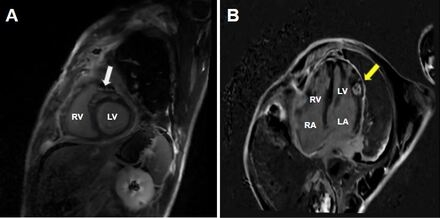

Case Presentation: ST-elevations on electrocardiogram are often due to cardiac emergencies such as a myocardial infarction. However, they may also signal a more occult pathology. A 35-year-old male with a past medical history of polysubstance-use disorder presented to the ED with a month-long history of chest and abdominal pain, and one day history of chest pain, orthopnea and respiratory distress. Initial vital signs significant for tachycardia to 124 bpm, otherwise normotensive, afebrile, and on room air. EKG notable for ST-elevations in the inferolateral leads. Ongoing symptoms, EKG changes, and elevated troponin prompted coronary angiography which showed no luminal disease. LVEDP was severely elevated (32 mmHg). Due to worsening respiratory distress, he was intubated and transferred to the cardiac critical care unit for suspected myocarditis. Cardiac MRI was significant for biventricular dysfunction (LVEF 30%, RVEF 32%), patchy late gadolinium enhancement (LGE) of both ventricles, and a well-circumscribed 15 mm x 15 mm region of LGE noted in the anterolateral myocardium consistent with an infiltrative mass, confirmed on CT chest imaging. Lymph node biopsy confirmed Classic Hodgkin Lymphoma. Incidentally, CT imaging of the abdomen also revealed a perforated abdominal viscous which was repaired laparoscopically. This surgery delayed systemic chemotherapy (ie high dose steroids) by 4 weeks. Patient was readmitted 3 weeks later with cardiogenic shock requiring vasopressors and intubation due to complete heart block and treated with a leadless pacemaker. Given this acute cardiac decompensation, endomyocardial biopsy was performed, revealing an aggressive B-Cell Lymphoma, thought to be a secondary primary lesion vs high-grade transformation. Patient underwent targeted radiation and multiple cycles of systemic chemotherapy, although course complicated by poor follow-up in the setting of polysubstance use and housing insecurity.